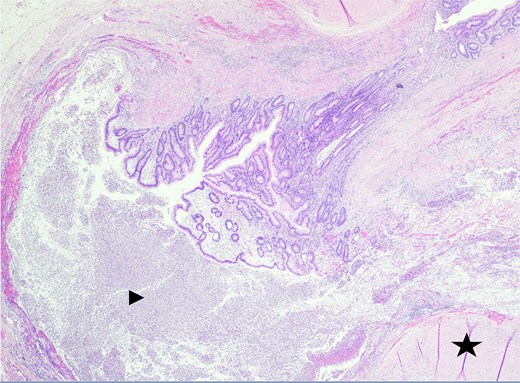

In the operating room, multiple adhesions from the patient’s prior colostomy site and colon resection were noted. The appendix was found to be dilated, acutely inflamed, and hyperemic, consistent with the suspected diagnosis of acute appendicitis. Adhesions from the appendix to the abdominal sidewall were dissected bluntly, pulling the appendix to a more medial position. The harmonic surgical device was used to divide the appendix mesentery and the gastrointestinal anastomosis (GIA) stapler with a blue load was used to divide the appendix from the base of the cecum. Final pathology showed an intact vermiform appendix measuring 6.5 × 1.5 cm with 3.2 × 2.5 × 1.6 cm portion of the attached mesoappendix. On gross examination, tan-pink hemorrhagic serosa with minimal adhesions and no exudate was noted. Sectioning of the specimen revealed a 0.5-cm in diameter lumen filled with a moderate amount of hemorrhagic purulent fecal material and at the distal tip, an intact diverticulum with wall measurement up to 0.2 cm in average thickness (Figs 1 and 2).

Sectioning of the intact vermiform appendix, bottom portion, with the appendiceal diverticula showing the muscularis propria (star) and acute inflammatory cells, neutrophils (arrowhead), within.